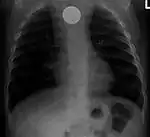

На рентгенограмме органов грудной полости (слева — в прямой, справа в боковой проекции) — видно инородное тело (монета) пищевода. | ||

Одна из распространённых локализаций инородных тел — желудочно-кишечный тракт. Возможные пути проникновения инородных тел — ротовая полость[13] или прямая кишка[14]. Дети чаще проглатывают монеты[15], у взрослых в 75% случаев инородными телами служили мясные кости[16].

Наиболее часто проглоченные предметы обнаруживают в пищеводе или желудке, реже в глотке или двенадцатиперстной кишке[17].